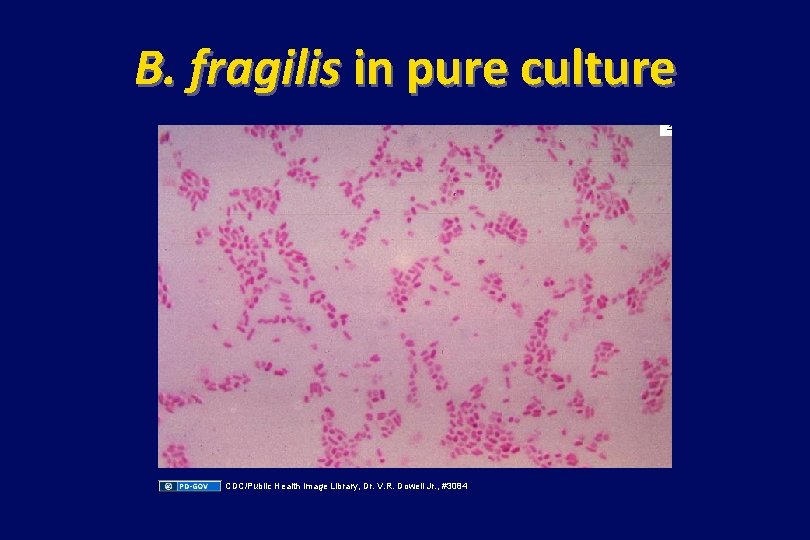

B. fragilis in pure culture CDC/Public Health Image Library, Dr. V. R. Dowell Jr. , #3084

Additional Source Information for more information see: http: //open. umich. edu/wiki/Citation. Policy Slide 10: Yu J, Fulcher AS, Turner MA, Halvorsen RA. Helical CT Evaluation of Acute Right Lower Quadrant Pain: Part I, Common Mimics of Appendicitis Am J Roentgenol. 2005; 184(4): 1136 -1142. Resource: medscape. com Slide 12: Source undetermined Slide 13: CDC: Public Health Image Library/Dr. V. R. Dowell, Jr. , 1972, http: //phil. cdc. gov/phil_images/20030203/6/PHIL_3084_lores. jpg Slide 31: Abhijit Datir, Lung Abscess, Radiopaeidia. org, http: //radiopaedia. org/articles/lung_abscess Slide 32: Source undetermined Slide 33: Source undetermined Slide 39 & 40: Lin D, Suwantarat N, Young RS. Lemierre’s Syndrome mimicking leptospirosis. Hawaii Med J. 2010; 69(7): 161 -63. http: //www. hawaiimedicaljournal. org/69. 07. 161. htm Slide 41: Source undetermined